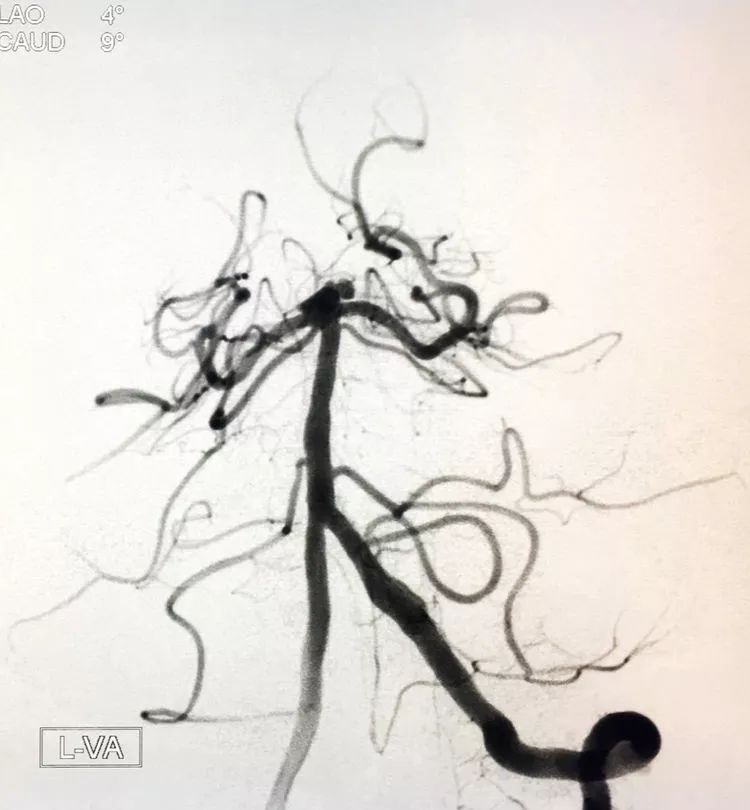

患者女性,80岁,以SAH于2017.5.20急诊入院,CTA示基底动脉顶端动脉瘤。

左椎动脉正位造影可以看到指向左方的子瘤。

术后左椎动脉正位、侧位的造影和蒙片